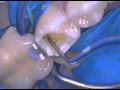

Възстановителна Дентална МедицинаИндиректно възстановяване на задни зъби под микроскоп – пълен протоколВидяно: 5558 пъти | Коментари: 0 |